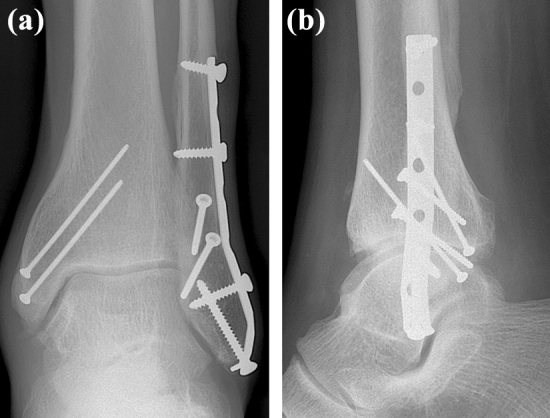

The patient was admitted to the hospital. The involved lower limb was elevated and analgesics were administered. Pain, swelling and paresthesia slightly subsided. The condition of soft tissues allowed definite operative treatment 13 days after the injury. First, reduction of the posteromedial fragment of the PM and fixation with 2 pins were performed from a posteromedial approach. In the next step, the distal fibular fracture was reduced via a lateral approach and fixed with two 2.7 mm lag screws and a 3.5 mm 1/3 tubular neutralization plate. The hook test performed at this stage showed instability of the tibiofibular mortise that was subsequently fixed by a 3.5 mm tibiofibular syndesmotic screw (Fig. 4).

Fig. 4.

Postoperative radiographs after open reduction and internal fixation